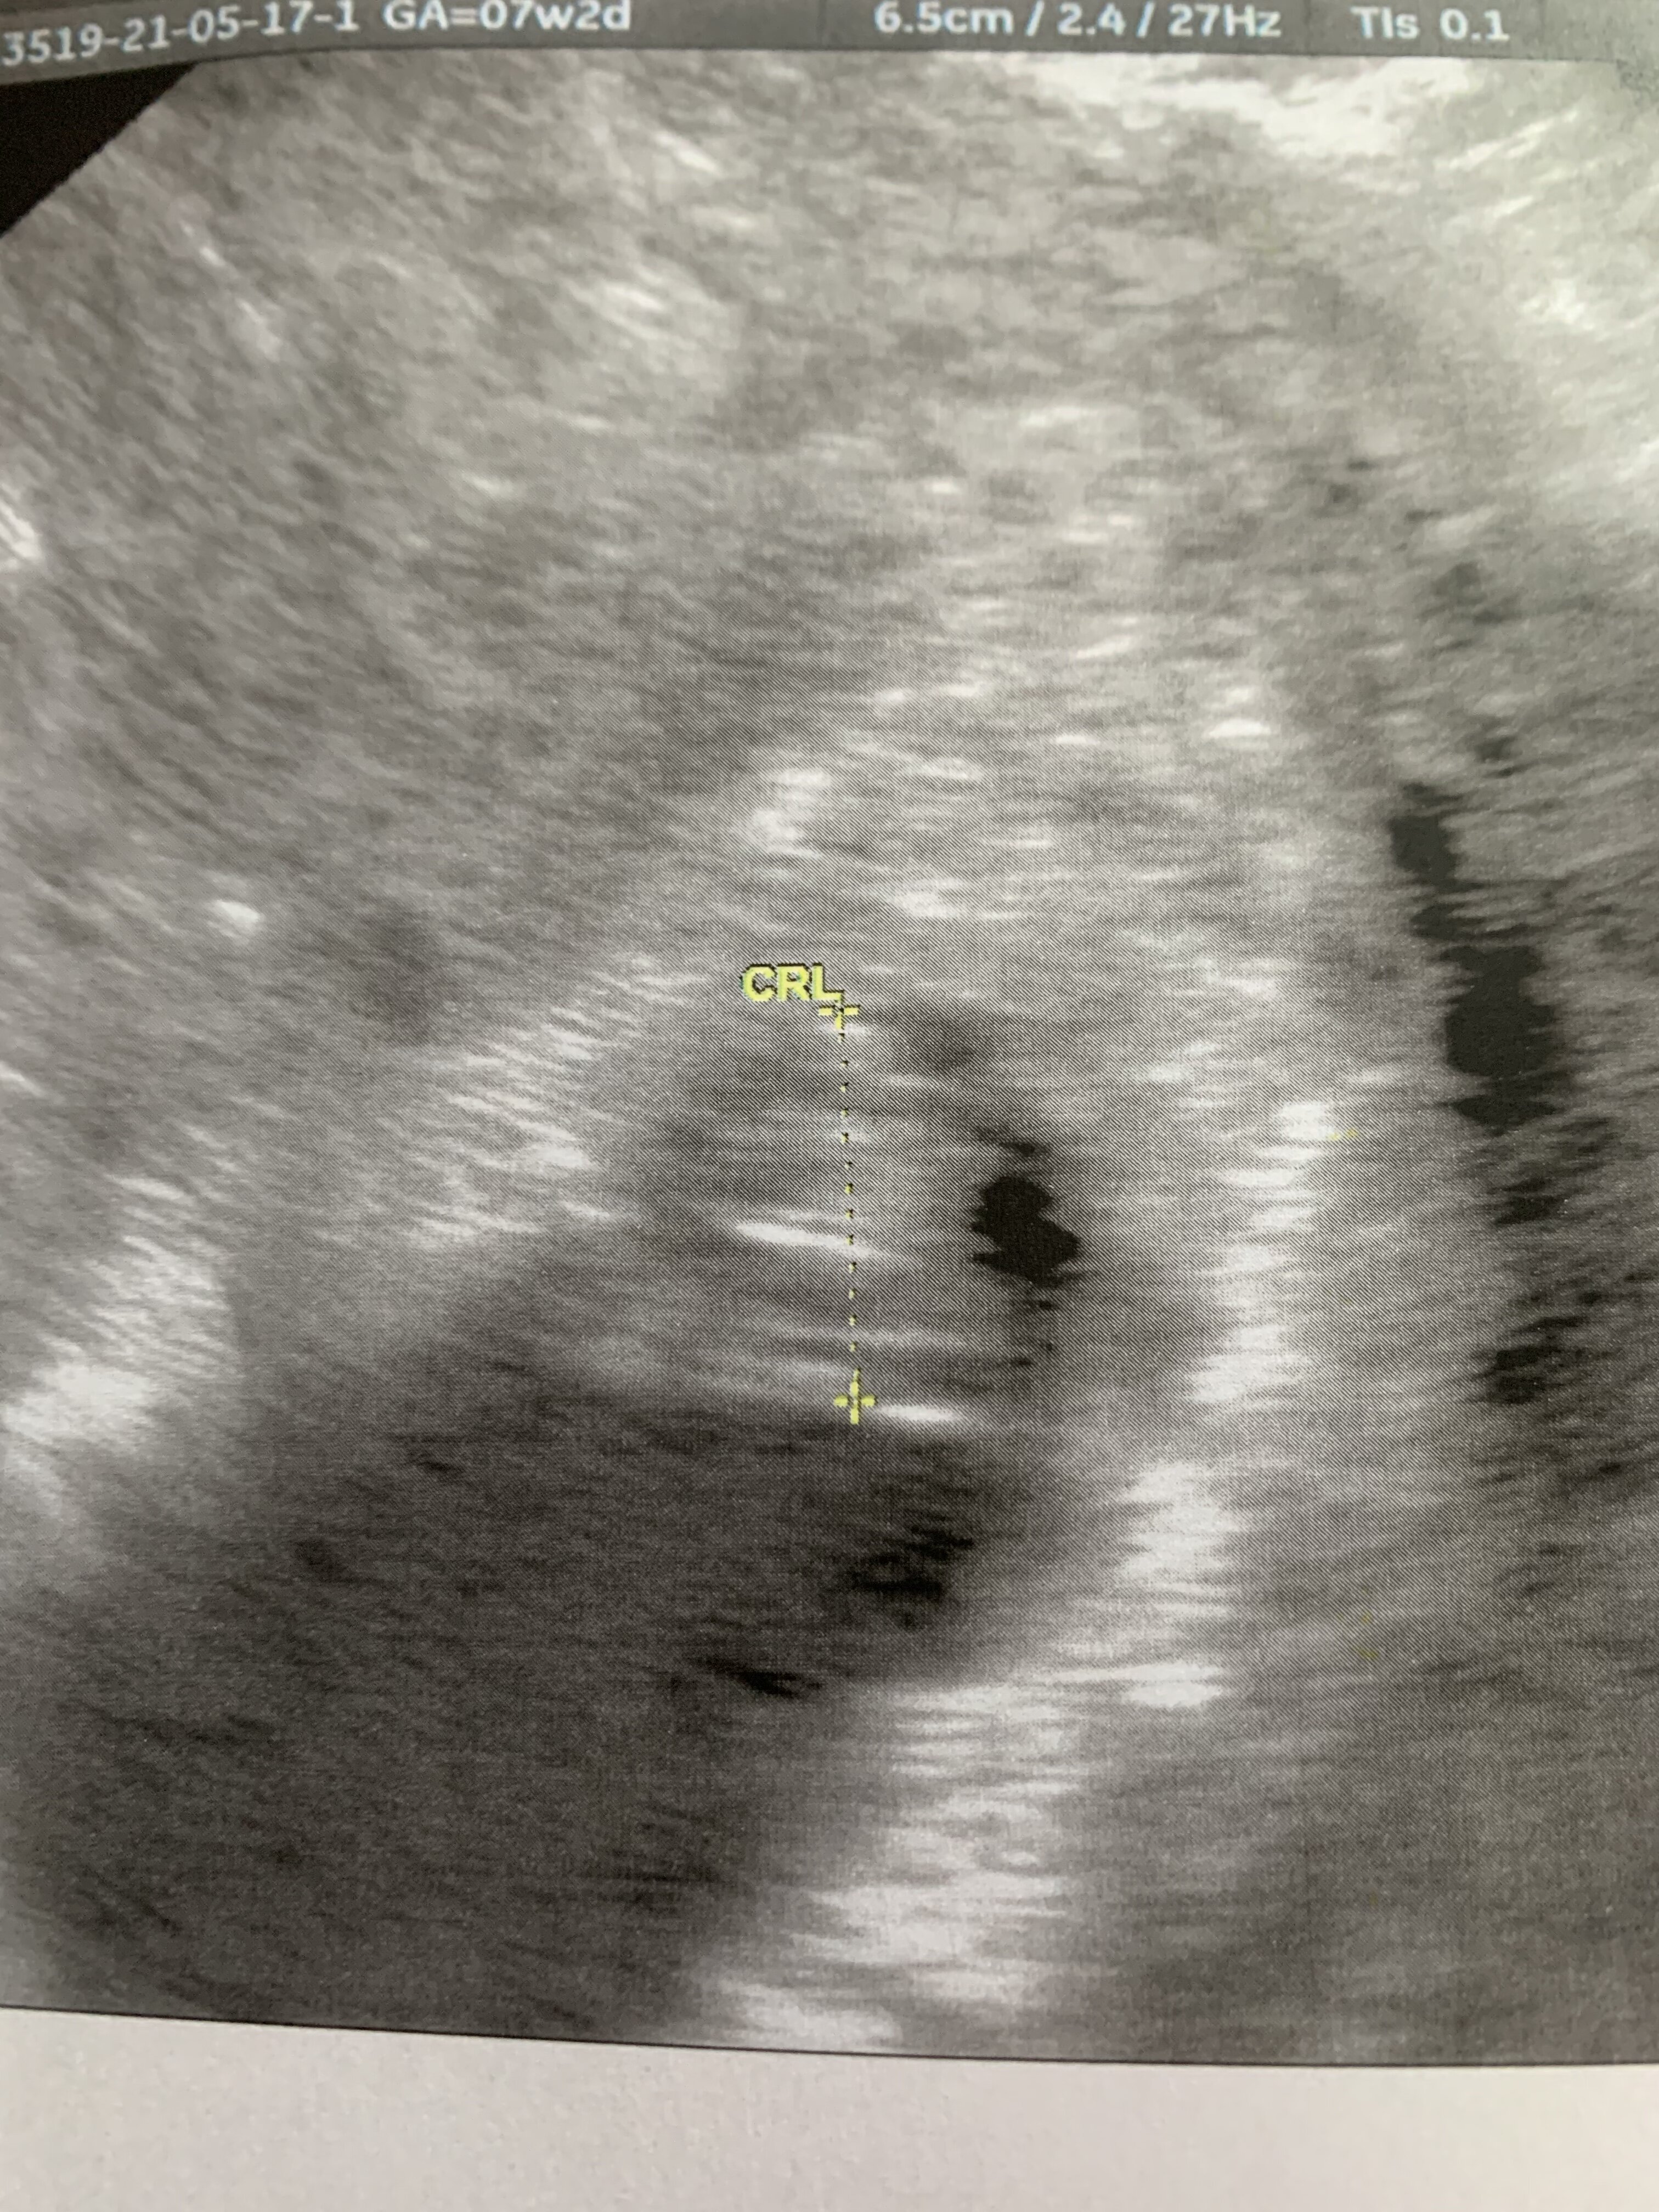

W ogóle jakie mega słabe zdjęcie 🙈

Załączniki

• 07BB00BD-A699-44CC-AA78-6716972FB666.jpeg

07BB00BD-A699-44CC-AA78-6716972FB666.jpeg

1,8 MB · Wyświetleń: 111